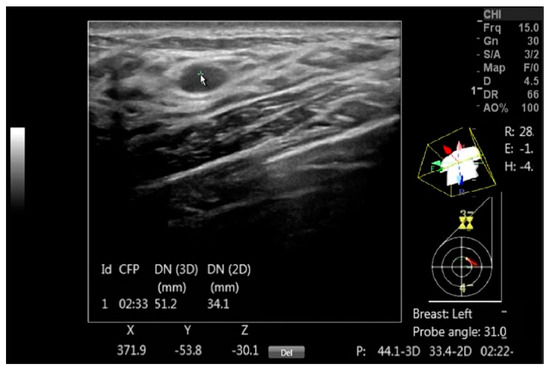

The DEVICE setup for automated breast mapping took less than a minute. By pointing to the center of a mass, automated positional data, including the mass center coordinates, probe position and rotation, and body rotation are instantly generated (Figure 2).

Figure 2.

A DICOM image with a benign mass is annotated using DEVICE to document the mass, with the arrow pointing to the mass. The on-screen information includes the clock face position (CFP), the 3D distance to the nipple (DN (3D)), its projection in the coronal plane (DN (2D)) and the Cartesian coordinates (X, Y, and Z) for each mass center point. Additionally, the display shows the probe head orientation over the diagram, the probe axis tilt in degrees and the body rotation relative to the exam table, which are marked as R, E and H and given in degrees.